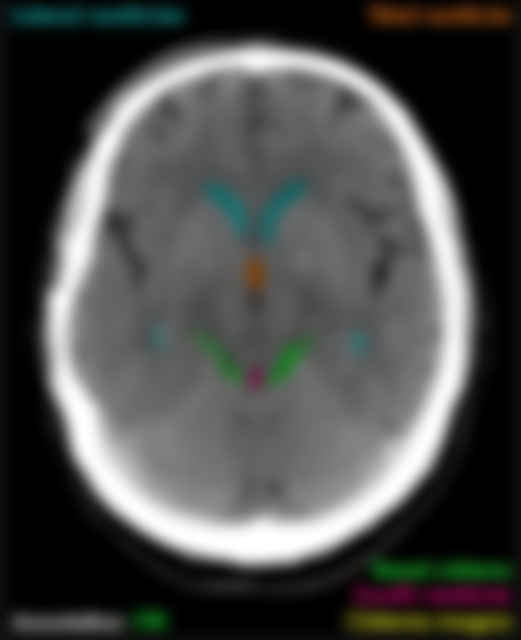

44 附圖中箭號所指的構造為何?

(A)第一腦室

(B)第二腦室

(C)第三腦室

(D)第四腦室